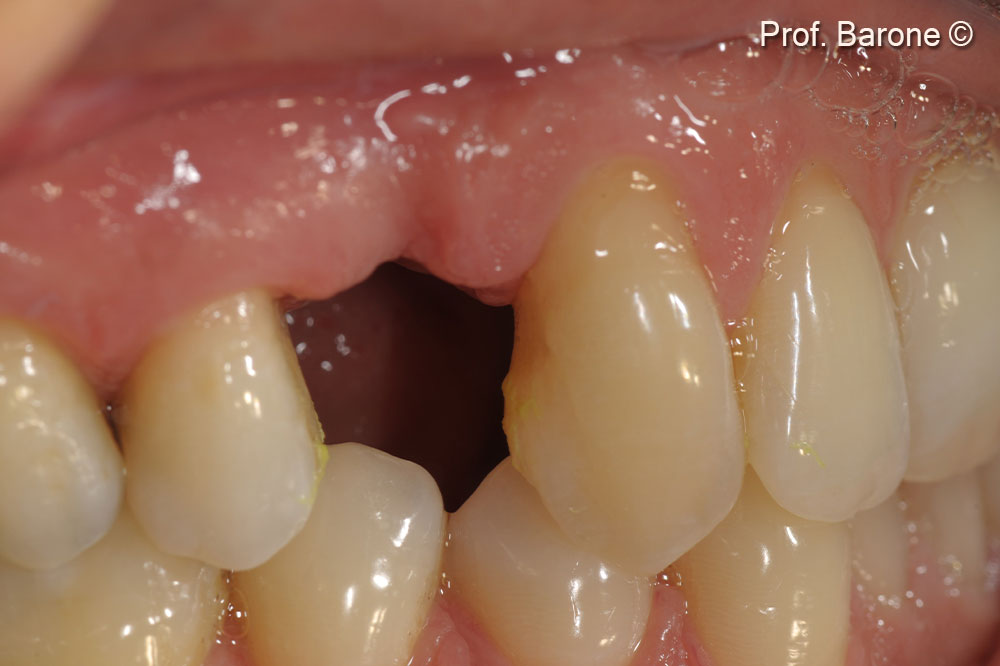

Clinical pre-operative lateral view of the tooth #24 (gingival recession and a fistula can be observed)